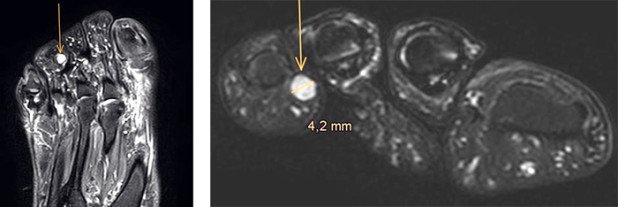

Als die Patientin erneut bei uns in der Fusschirurgie vorstellig wurde, konnte sie den Schmerz gut an der Innenseite der Zehenspitze lokalisieren. Bei der Untersuchung liess sich an dieser Stelle in den Weichteilen eine kleine kugelige, stark druckempfindliche Struktur tasten. Bei Durchsicht des mitgebrachten MRI konnten wir eine dazu passende Formation von ca. 4 mm Durchmesser identifizieren.

Rechts: Die Grösse des Tumors konnte mit ca. 4 mm bestimmt werden.